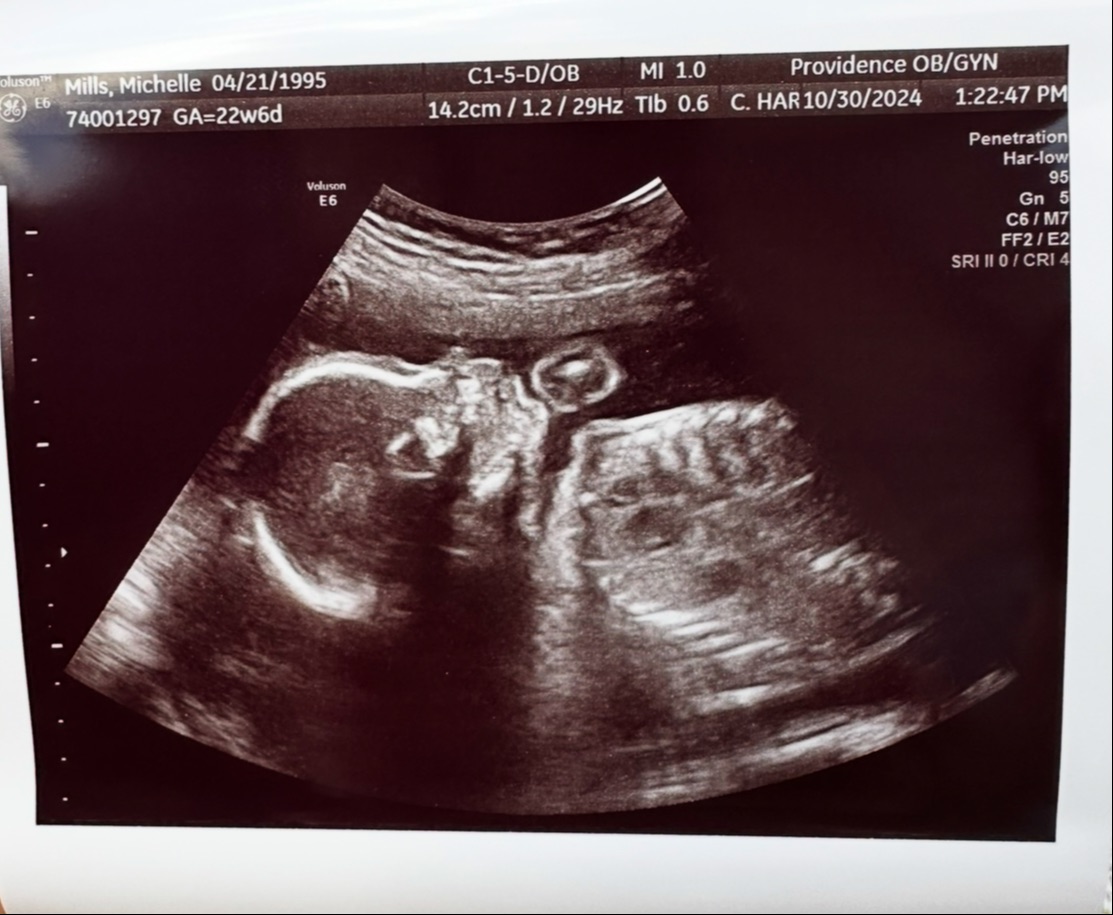

Carmia Daisie Jordan

March 5, 2025

7lb 13oz, 21 inches long